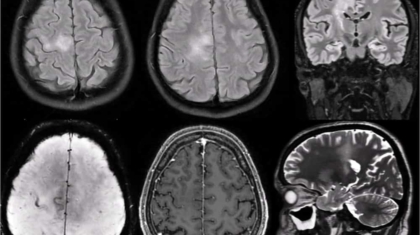

*39 year man

*K/c/o of Type 2 DM

*Newly diagnosed microcytic anemia

*Progressive weakness of left upper limb and lower limb past 6 months

*Involuntary movements of left hand